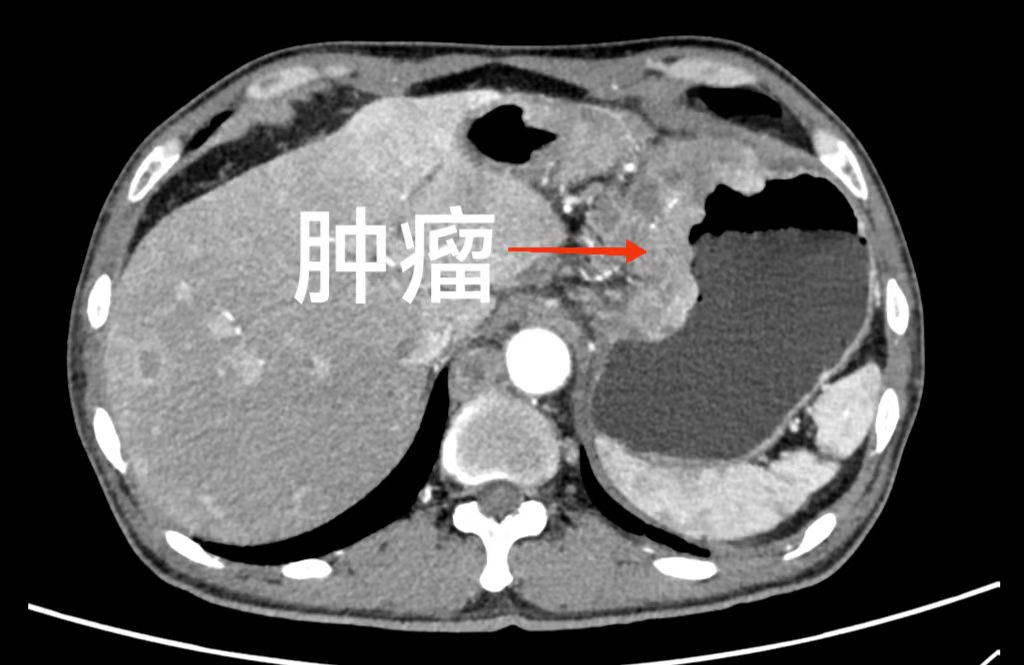

李丹主任仔细检查完患者身体并结合胃镜检查后认为:患者目前胃癌诊断明确,且发现左锁骨下肿大淋巴结,考虑胃癌晚期并远处淋巴结转移。建议患者先行左锁骨下肿大淋巴结穿刺活检,明确诊断。

李丹主任指示:目前患者诊断明确,胃癌晚期并远处淋巴结转移,直接手术效果不佳,建议先行转化治疗,可以有效的增加患者术后生存时间。

转化治疗就是对于那些无法完整切除的肿瘤患者,通过术前的辅助治疗,转化为可以手术的患者。